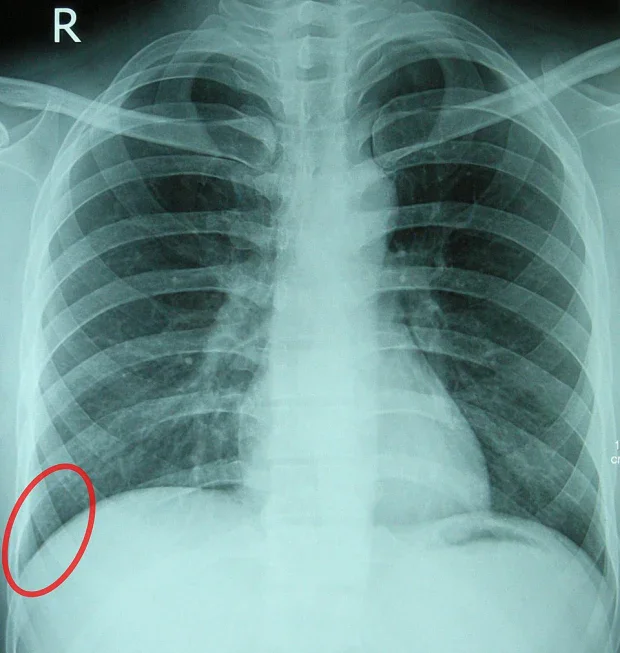

Костно-диафрагмалните синуси (КДС, КД синуси, recessus costodiaphragmaticus) - Това са най-ниско разположените части на плевралната кухина, където ребрената плевра преминава в диафрагмалната плевра. Те се намират в най-долната част на гръдния кош, между ребрата и купола на диафрагмата. Коагто са в норма на рентгенова снимка, тези синуси изглеждат като остри ъгли. Ако ъгълът е заоблен или липсва, това често е признак за патологичен процес. Свободните синуси (свободни КДС) са нормална находка, показваща, че няма събрана течност или сраствания.